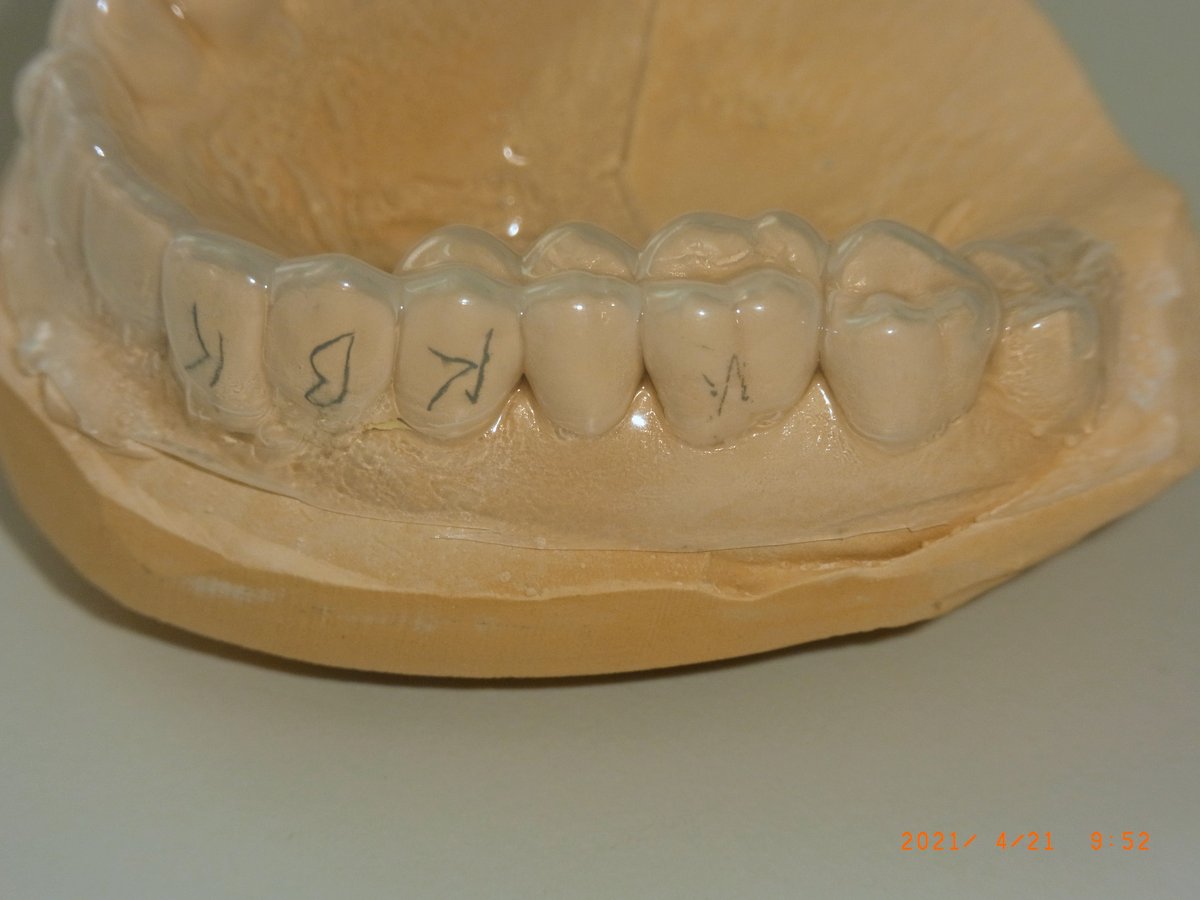

Vorabformung mit knetbarem Silikon im Rim-Lock-Einmalplastiklöffel (Fa. Dental Contact) auf dem Gipsmodell. Das knetbare Material füllt den Löffel über die Tiefziehfolie blasenfrei aus.

Fertiger KIL (links) neben dem Gipsmodell mit aufgezogener Tiefziehfolie (rechts). Der Löffel wird bis zu einige Tage vor der Verwendung im Eigenlabor gefertigt. Beschnitten wird der KIL im späteren Stumpfbereich gar nicht; in den übrigen Bereichen oral und lingual mit einem scharfen Küchenmesser bis ins gingivale Drittel der Zähne.